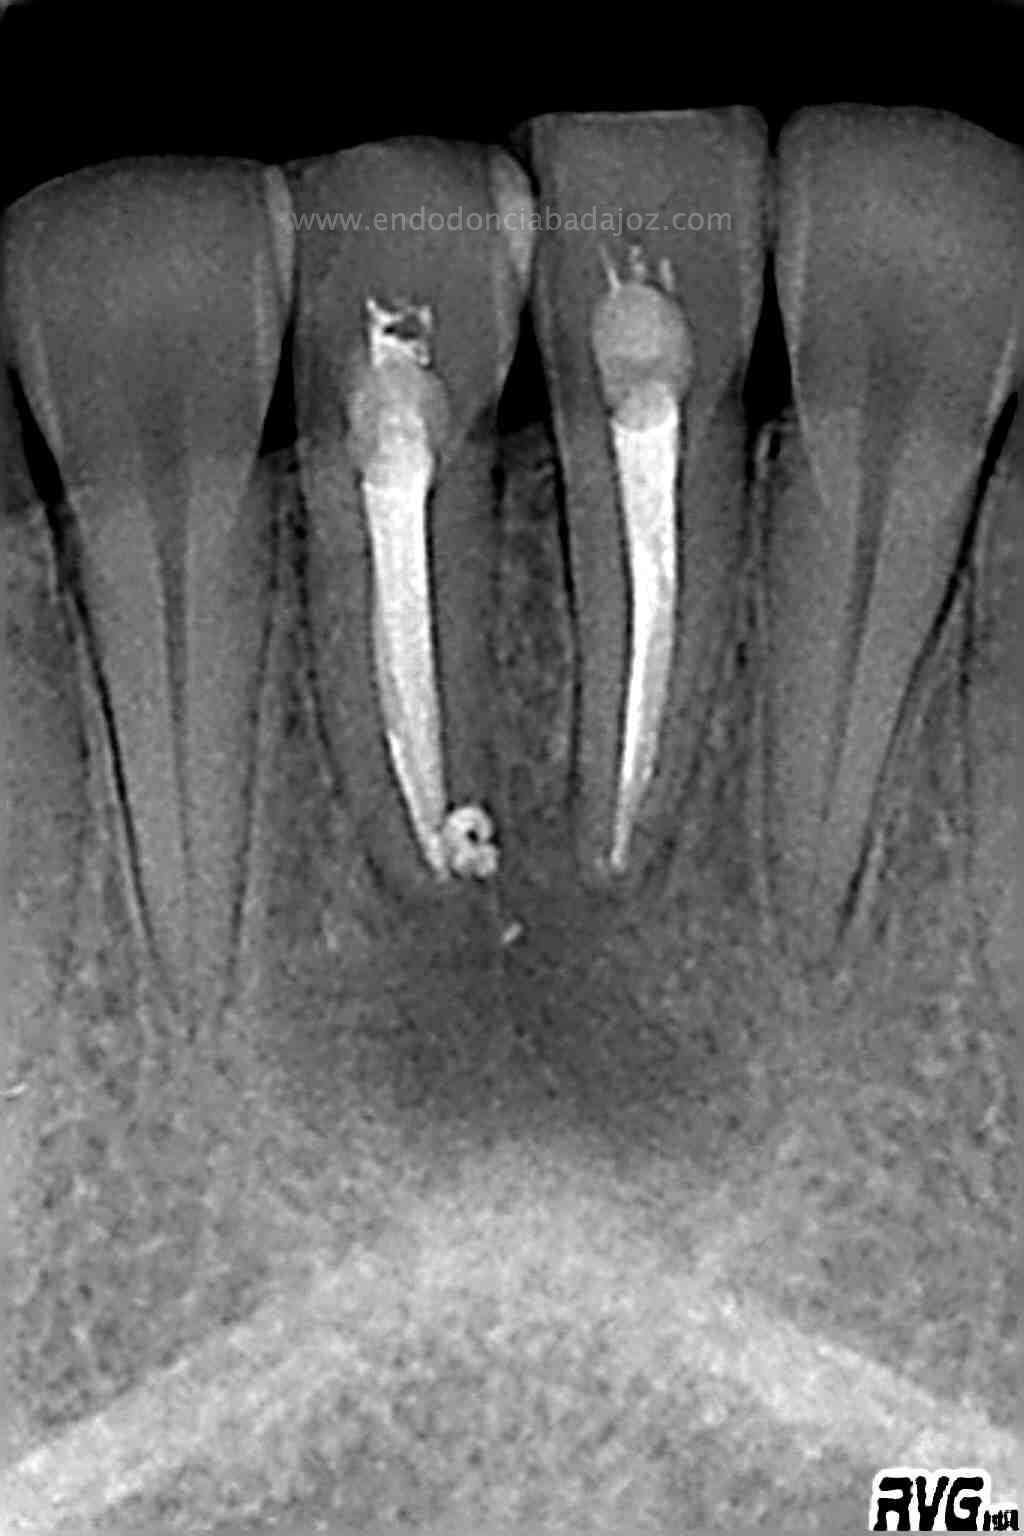

En una segunda sesión, obturamos los conductos tridimensionalmente, conductos acintados. Usaríamos la técnica de Ola continua de Buchanan haciendo un backfilling con la Pistola ObturaII:

Debido al estudio anteriormente citado, se empezó a hacer el tratamiento de ortodoncia una vez que se comenzó a ver una evolución positiva, con signos claros de regeneración a los 6 meses .

(revisión a los 6 meses)